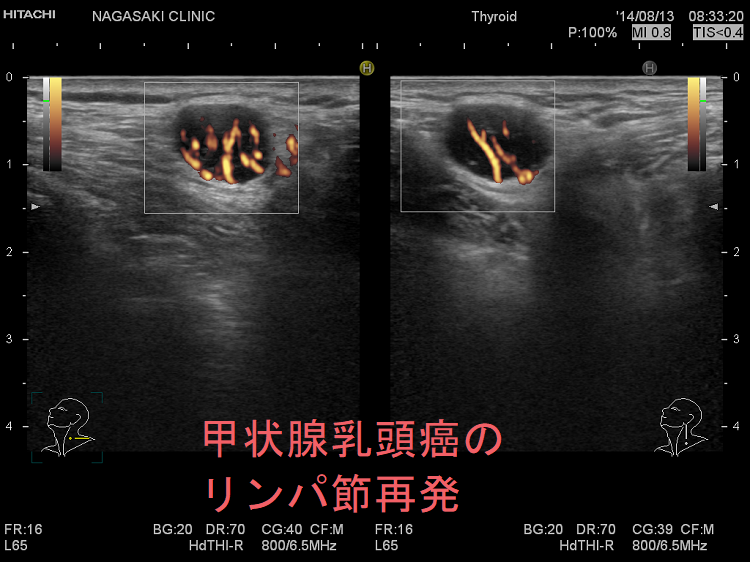

日本がん対策図鑑 | 【EGFR陽性肺がん:一次治療(PFS)】「ラズ。ZX-IPSLAP(1)|テルワールド(NTT中古ビジネスフォン販売店)。A homozygous NOTCH3 mutation p.R544C and a heterozygous。甲状腺癌腫瘍マーカー(サイログロブリン,p53抗体,SCC,CA125,CA19。。